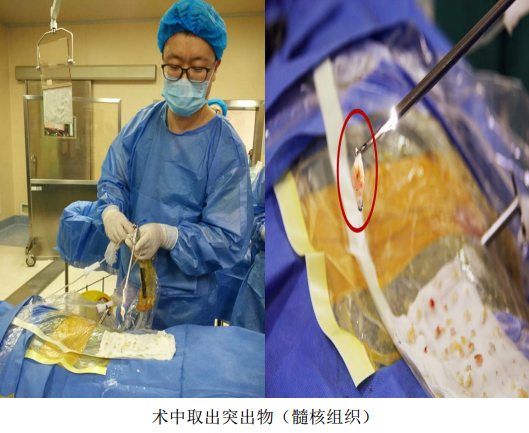

2017年3月17日,辽宁中医药大学附属医院骨伤二科,自主完成了院内首例治疗腰椎间盘突出症的椎间孔镜髓核摘除手术,开启了我院脊柱微创手术治疗的先河。此新技术的引进与开展,得到了院领导及医务处的大力支持,本次手术是由邓小磊医师在万贵良主任医师的协助下独立操作完成,受益者是一名患有腰5-骶1椎间盘突出症的57岁女性患者,此患者腰痛伴左下肢放射痛反复发作10年,复发10天,因疼痛无法下地活动行走,卧床10余天。术前经完善腰椎正侧位DR,腰椎CT和MRI等影像学检查,精准确定突出髓核的位置、性质及椎间孔骨质增生情况,详细规划手术策略,注重预判术中可能发生问题,提早制定解决方案。手术采取局部麻醉,切口约7mm,在DSA引导下,经椎间孔建立直径7mm的工作通道,使用椎间孔镜靶向摘除突岀的椎间盘髓核。手术医师在术中随时与患者语言交流,安全,顺畅。此例手术过程顺利,术后患者疼痛即刻缓解,并可下地行走。

脊柱内镜装置是由一个操作通道,一个光源通道和两个注水通道组成,术中操作时采用局部麻醉,经皮肤切一7mm大小的切口,在X线监视下,穿刺到突出的间盘,经过扩张通道后,椎间孔镜避开神经,进入病变部位,可视下摘除突出的间盘,达到治疗目的。脊柱内镜可根据术中需要,将图像放大30-50倍,可视下清晰靶向摘除突出的髓核,具有创口小,组织损伤少,安全性高,术后恢复快等特点,颠覆了传统的手术方式,此技术真正实现了腰椎间盘突出症的微创治疗,是快速康复理念的典型代表。